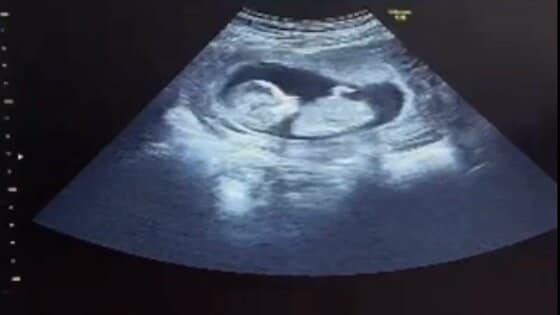

子宮がんで突然の「産めない」宣告 残された5つの受精卵、夫… ギャラリー 1/10 記事に戻る 「我が子」のエコー 2/10 記事に戻る 裕太さんと優美さん 3/10 記事に戻る 診断書 4/10 記事に戻る 優美さんのお腹に残る手術の痕 5/10 記事に戻る 夫婦に残された5つの受精卵 6/10 記事に戻る 「代理出産」の仕組み 7/10 記事に戻る 2人が見つめるエコー動画 8/10 記事に戻る 特別養子縁組の手続きを踏んで正式に「親子」となる 9/10 記事に戻る 出産の知らせを待つ2人 10/10 記事に戻る